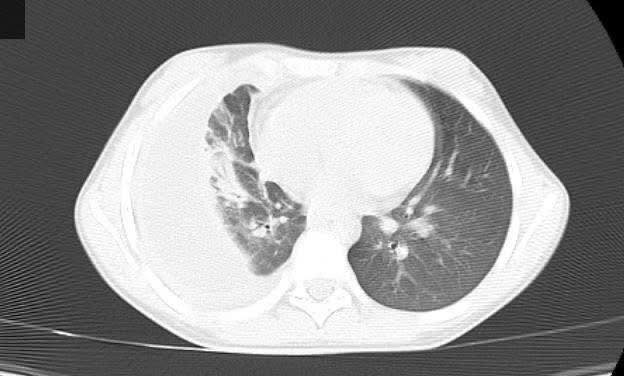

viem-mu-mang-1.jpg

Viêm phổi trên phim chụp cắt lớp vi tính - Ảnh BVCC

Phẫu thuật nội soi giúp loại bỏ mủ trong khoang màng phổi, thông thoáng đường hô hấp và giúp bệnh nhi dễ dàng thở hơn, đã mở ra một cơ hội mới cho các bệnh nhi mắc bệnh lý này, giúp nâng cao hiệu quả điều trị, giảm thiểu các rủi ro và mang lại cuộc sống khỏe mạnh cho các em.